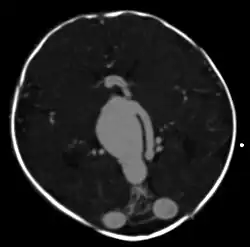

Axial image from computerized tomography angiogram showing arteriovenous communication in

vein of Galen malformation

Vein of Galen thrombosis from ventricular puncture, not to be mistaken for an aneurysmal malformation

A cerebral AVM diagnosis is established by neuroimaging studies after a complete neurological and physical examination.[5][13] Three main techniques are used to visualize the brain and search for an AVM: computed tomography (CT), magnetic resonance imaging (MRI), and cerebral angiography.[13] A CT scan of the head is usually performed first when the subject is symptomatic. It can suggest the approximate site of the bleed.[3] MRI is more sensitive than CT in the diagnosis, and provides better information about the exact location of the malformation.[13] More detailed pictures of the tangle of blood vessels that compose an AVM can be obtained by using radioactive agents injected into the blood stream. If a CT is used in conjunction with an angiogram, this is called a computerized tomography angiogram; while, if MRI is used it is called magnetic resonance angiogram.[3][13] The best images of a cerebral AVM are obtained through cerebral angiography. This procedure involves using a catheter, threaded through an artery up to the head, to deliver a contrast agent into the AVM. As the contrast agent flows through the AVM structure, a sequence of X-ray images are obtained.[13]